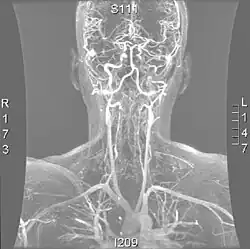

Os métodos mais modernos envolvem angiografia por tomografia computorizada, denominada angiotomografia (ATC ou angio-TC) — e ressonância magnética (RM). Estes métodos requerem uma menor quantidade de contraste e não são invasivos. A angiografia por TAC e a angiografia por RM são mais ou menos equivalentes quando usadas para diagnosticar ou excluir uma dissecção da artéria vertebral.[13] A ATC tem a vantagem de mostrar certas anormalidades mais cedo, tende a estar disponível fora do horário de expediente e pode ser realizada rapidamente.[1] Quando a angiografia por RM é usada, os melhores resultados são obtidos no cenário T1[2] usando um protocolo conhecido como "supressão de gordura".[3] A ecografia Doppler é menos útil, pois fornece poucas informações sobre a parte da artéria próxima à base do crânio e no forame vertebral, e qualquer anormalidade detectada na ecografia ainda exigiria confirmação através de um TC ou RM.[1][2][3]